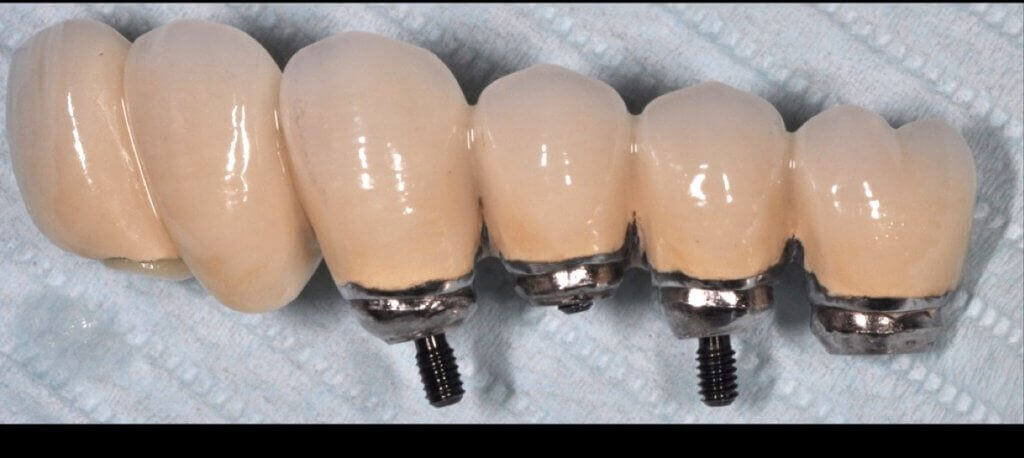

A proper emergence profile is the one that allows direct access to the top of the sulcus and the “danger zone” all around the prosthesis. On the contrary, a typical prosthesis design that blocks access to the sulcus is the “ridge lap”. A ridge lap is a horizontal extension of the prosthesis starting from the top of the sulcus and “riding” the alveolar ridge in mesiodistal or palatolingual direction. We commonly assess the emergence profile in the mesio-distal direction (probably because this is what radiographs show us), but ridge lap is very common (and thus damaging) in the bucco-palatal dimension, too. A recent study by Katafuchi et al, actually showed how the concavity of the emergence profile is important (with concave profile better to convex) and with an emergence angle of more than 30 degrees being significantly correlated with peri-implantitis.

But if nobody likes a ridge lap, why do we keep seeing it so often?

There is only one reason: ridge lap is a compensation for compromised implant selection or position. What are the most common reasons for a ridge lap today:

- a narrow implant platform selected for the replacement of a wide tooth. This is to be perceived both in mesio-distal and palato-lingual dimensions.

- too shallow implant placement. This is very commonly encountered in the upper anterior sites, where the implant is typically to be placed below the mesial and distal bone margins (a).

- too palatal placement, again very common in the upper anterior sites, where the bone resorption pattern eliminates much of the buccal ridge (b) (Photo courtesy Dr. M Janda).

- too palatal angle of placement (c).

- wrong mesio-distal position (c).